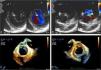

This morphology is completely different from the clefts observed in structurally normal mitral valves, which are more common in the anterior leaflet and the solution of continuity not only does not divide the leaflet into two separate parts but is oriented towards the left ventricular outflow tract (Figure 2).

(A and B) Two-dimensional transesophageal echocardiography, transgastric view, showing mitral valve anterior leaflet cleft (*) in diastole (A) and in systole (B); (C and D) real-time three-dimensional zoom, cropped images: in diastole, anterior leaflet cleft in atrial view (C) and ventricular view (D). Note the typical orientation of the cleft towards the left ventricular outflow tract.